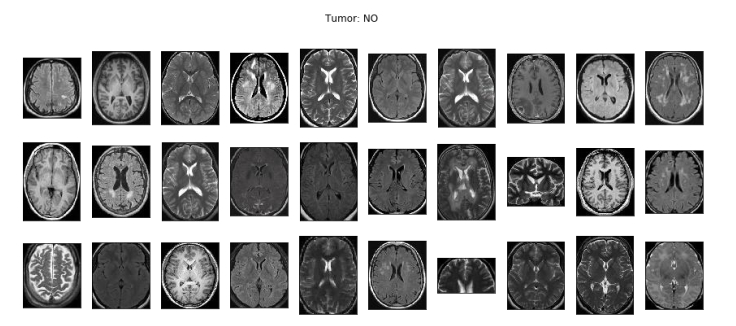

[46] R. Ranjbarzadeh, A. Keles, M. Crane, M. Bendechache, Comparative analysis of real-clinical MRI and BraTS datasets for brain tumor segmentation, CP887, IET, (2024), pp. 39–46.

[48] S. Suchitra, Parkinson disease prediction using deep learning algorithm, rp-9788770040723.217.

[55] R. Ranjbarzadeh, A. Caputo, E. B. Tirkolaee, S. J. Ghoushchi, M. Bendechache, Brain tumor segmentation of MRI images: A comprehensive review on the application of artificial intelligence tools, Comput. Biol. Med., 152 (2023), 106405. https://doi.org/10.1016/j.compbiomed.2022.106405 doi: 10.1016/j.compbiomed.2022.106405

[61] N. T. Sarshar, S. Sadeghi, M. Kamsari, M. Avazpour, S. J. Ghoushchi, R. Ranjbarzadeh, Advancing brain MRI images classification: Integrating VGG16 and ResNet50 with a Multi-verse optimization method, (2024).

[62] R. Ranjbarzadeh, A. B. Kasgari, S. J. Ghoushchi, S. Anari, M. Naseri, M. Bendechache, Brain tumor segmentation based on deep learning and an attention mechanism using MRI multi-modalities brain images, Sci. Rep., 11 (2021), 10930. https://doi.org/10.1038/s41598-021-90428-8 doi: 10.1038/s41598-021-90428-8

[68] A. B. Kasgari, R. Ranjbarzadeh, A. Caputo, S. B. Saadi, M. Bendechache, Brain tumor segmentation based on zernike moments, enhanced ant lion optimization, and convolutional neural network in MRI images, in: Metaheuristics and Optimization in Computer and Electrical Engineering, Hybrid and Improved Algorithms, Springer, 2 (2023), pp. 345–366.

[73] R. Ranjbarzadeh, M. Crane, M. Bendechache, The impact of backbone selection in Yolov8 Models on brain tumor localization, Iran J. Comput. Sci., (2025), 1–23. https://doi.org/10.1007/s42044-025-00258-4 doi: 10.1007/s42044-025-00258-4

[75] R. Ranjbarzadeh, A. Keles, M. Crane, S. Anari, M. Bendechache, Secure and decentralized collaboration in oncology: A blockchain approach to tumor segmentation, IEEE, 2024, pp.1681–1686.